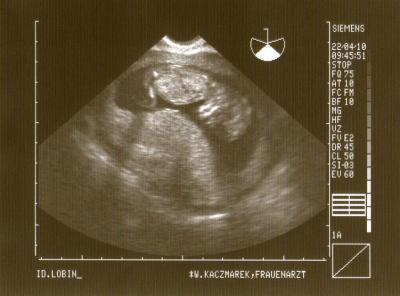

...mit guuuten neuigkeiten! ich war ja heute morgen aufgrund meiner beschwerden beim FA. er hat auch gleich nachgeschaut, muttermund usw. alles in ordnung und dann hat er auch gleich noch einen us gemacht. ...dabei hat er nicht schlecht gestaunt, denn der zwerg ist schon gute 6 cm ssl groß und das bei 11+5. da haben wir dann wohl die ursache, mein wurm hatte wohl einen ordentlichen wachstumsschub und das ist dann natürlich nicht so angenehm, es drückt alles und die bänder ziehen. mein wurm hat geschlafen und der fa hat ihn dann mal kurz angestubst, da hat er sich auch gleich bewegt, so nach dem motto:"was soll das denn jetzt hier?!" trotzdem musste ich vorsichtshalber noch urin abgeben, aber auch der befund war unauffällig. nächste woche habe ich ganz normal die VU und hier ist das neuste bildchen! (mein mäuschen hat schon einen netten pullerbauch! )

Bild zu Zurück vom FA - Forum für November - Mamis

laut der größentabelle bin ich bei 12+5, also eine woche weiter! genauso wie bei meiner tochter damals. meine tochter kam 2 wochen eher, hmm mal schauen ob es nicht vielleicht noch ein oktoberzwerg wird!